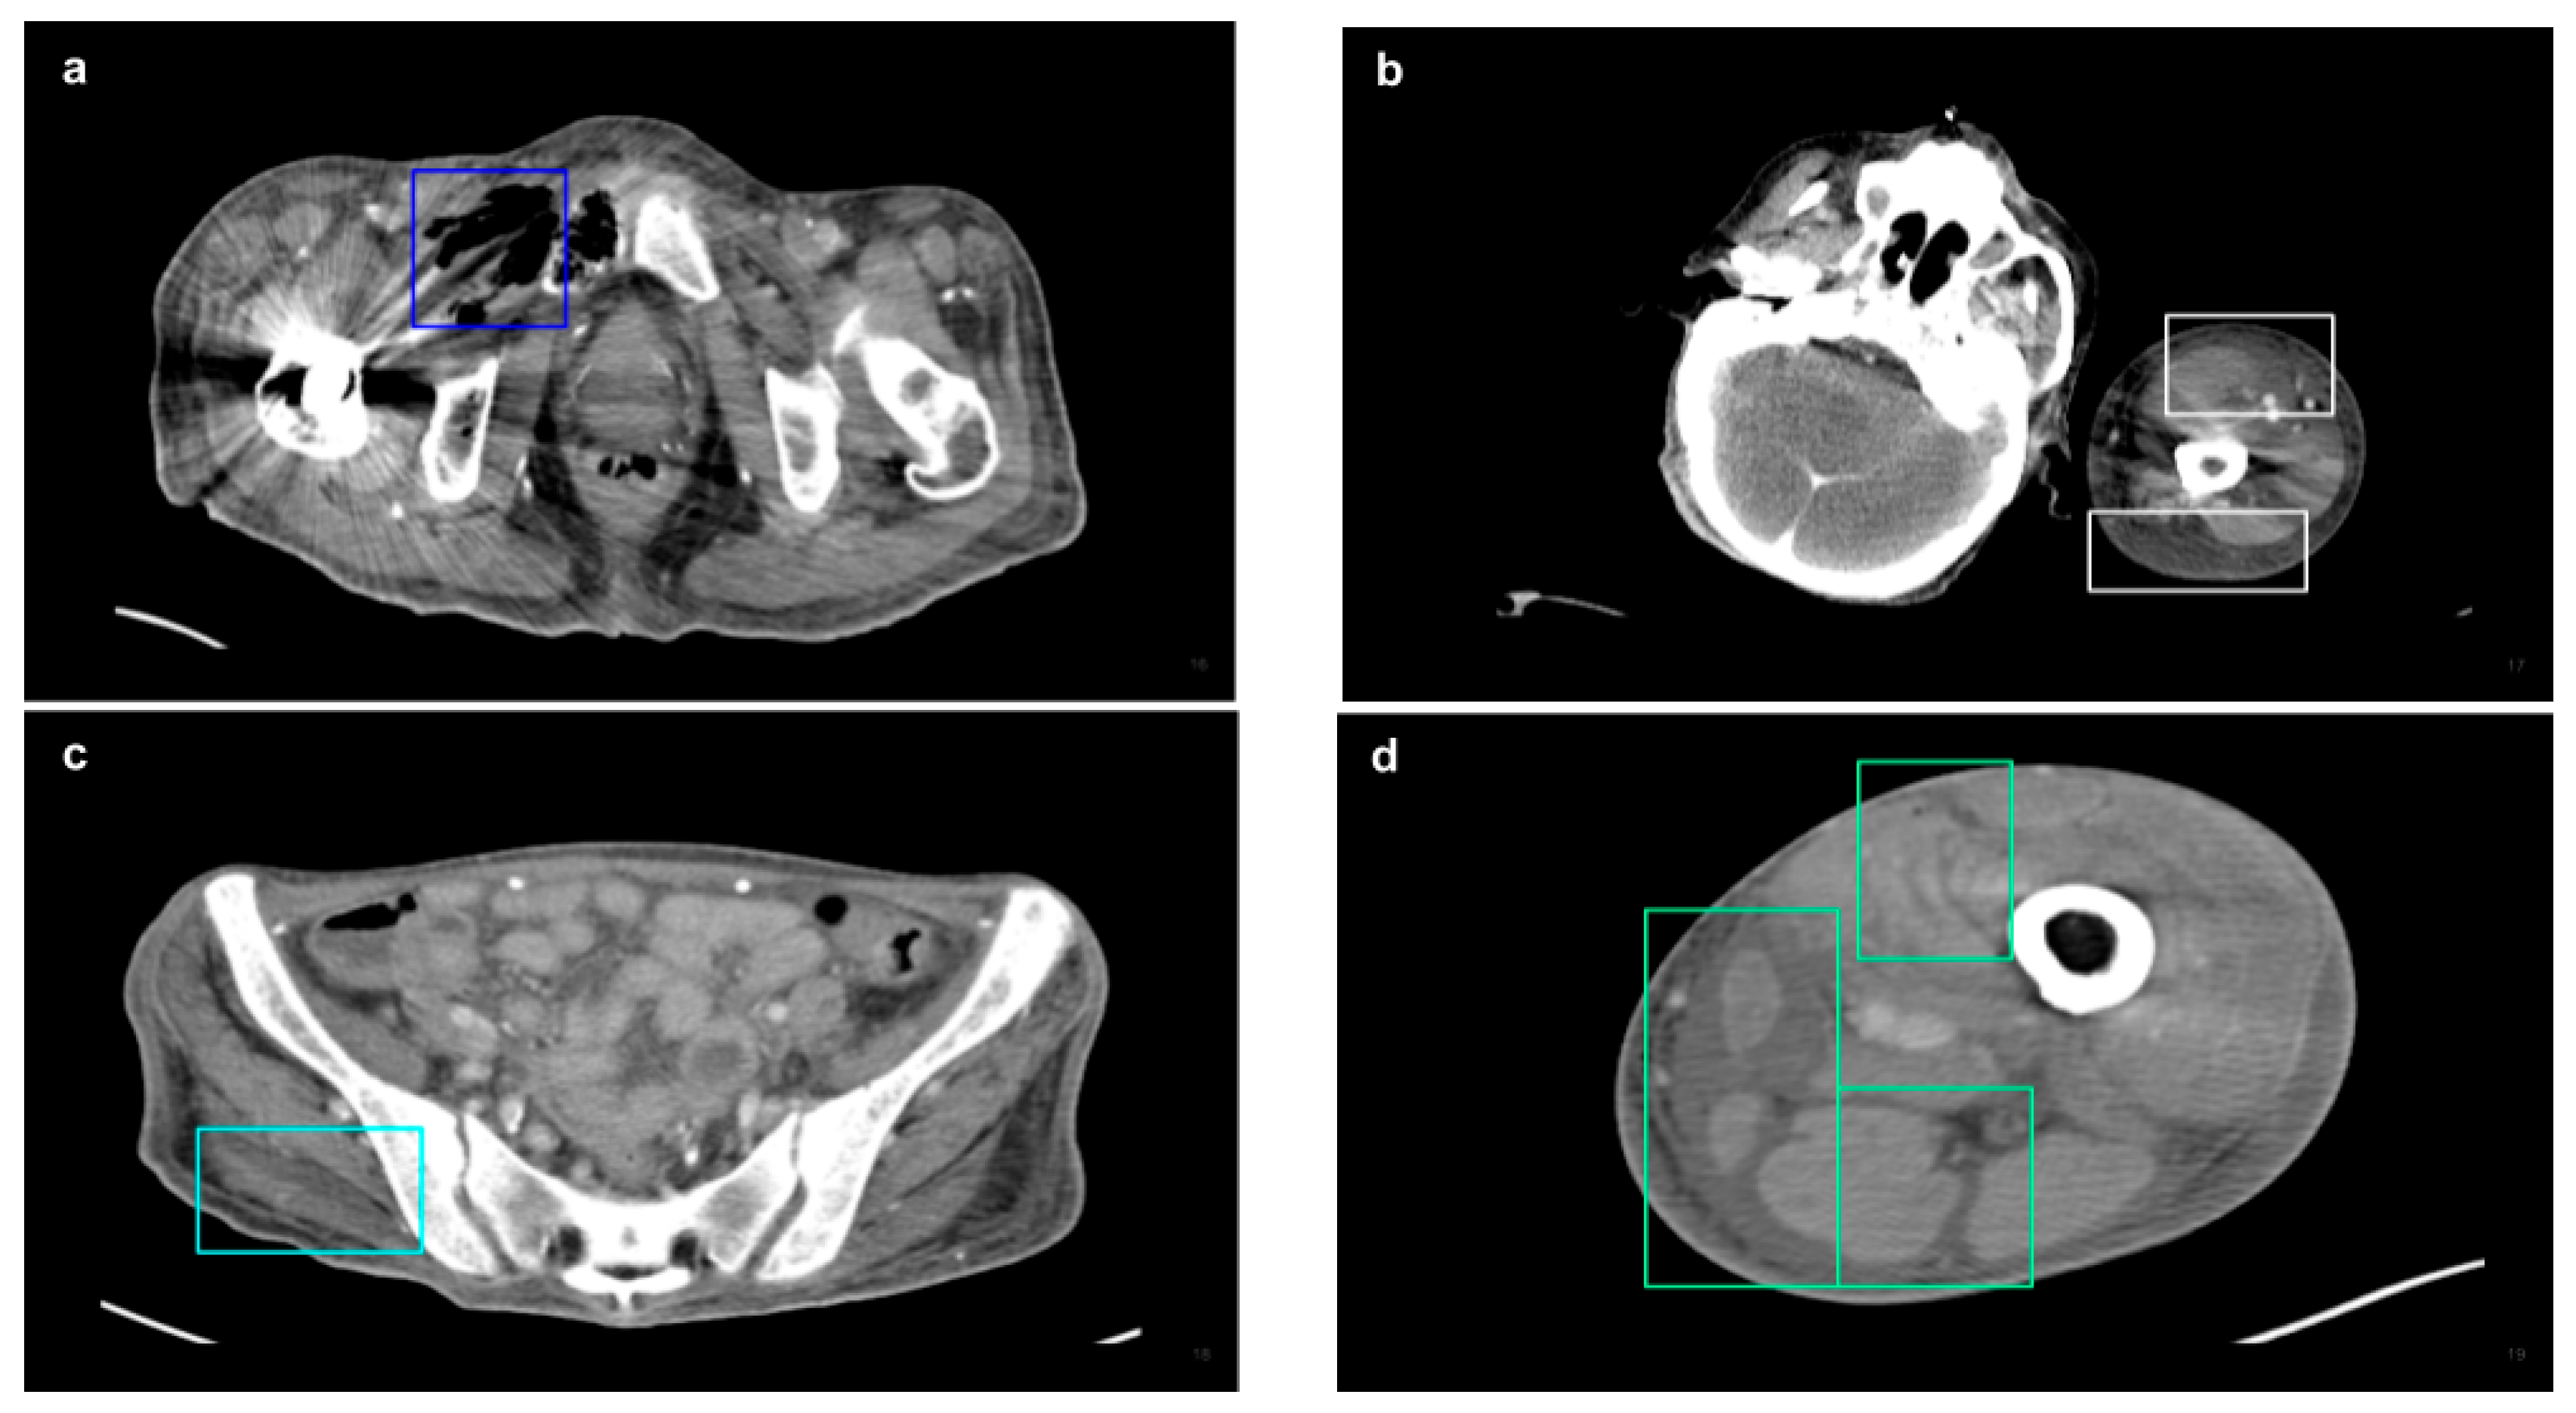

| NSTI features | ||

| Soft tissue ectopic gas | 1982 | 33.13% |

| Fluid accumulation | 1577 | 27.04% |

| Fascia edematous changes | 1872 | 32.10% |

| Soft tissue non-enhancement | 401 | 6.88% |